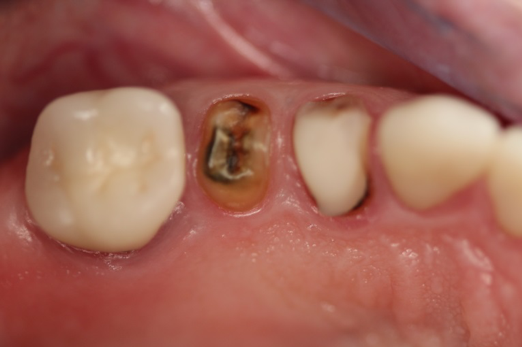

Fig 18. Preoperative image.

Figure 18

Occasionally dentists are presented with extreme challenges with long-term restorations and replacing missing teeth. Dentists must evaluate the patient's condition, develop optimum long-term oral health, and attempt to meet the patient's expectations. Figure 18 showed a class III malocclusion with deep bite, multiple abfractions, and less-than-ideal occlusal plane, but the patient wanted to replace his maxillary right canine only. A discussion with the patient regarding occlusal disharmonies and comprehensive recommendations for full-mouth rehabilitation revealed that the patient had a limited budget for dental care. The patient understood the ramifications of his comprehensive dental needs not being affordable. Decisions were made to atraumatically remove the maxillary right canine (Figure 19) and immediately place a ceramic dental implant (Figure 20). Polytetrafluoroethylene (PTFE) 4-0 sutures were placed to help support soft tissues, and then a full-arch Essix-style retainer with a flowable composite facial veneer was used to provide some esthetics during the patient's healing phase (Figure 21). The implant and the retainer were not to be in contactthe retainer may occlude with the opposing dentition and also be passive in relation to the ceramic implant.